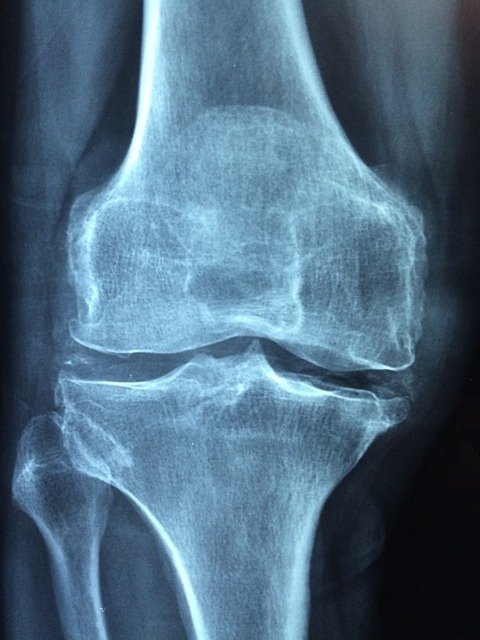

Diagnosticiranje osteoporoze

Danes se diagnoza osteoporoza postavi s pomočjo merjenja mineralne gostote kosti in sicer z DEXA(dvojna rentgenska absorpciometrija), lahko pa tudi na osnovi že dokazanih zlomov, ki so nastali zaradi osteoporoze. Obstajajo pa še številne druge metode merjenja kostne gostote, celo na kožni gubi. Tudi odvzem krvi, s katerim določimo kalcij, magnezij, fosfat, alkalno fosfatazo, TSH in pri moških testosteron, nam pove kakšno je gostota naših kosti, oziroma z njimi izključimo sekundarno osteoporozo, ki je nastala zaradi drugih bolezni oziroma zdravil. Ko je diagnoza postavljena je nujno začeti z zdravljenjem osteoporoze in sicer z zdravili, ki preprečujejo razgradnjo kosti, pri ženskah tudi z nadomestnim hormonskim zdravljenjem. Ravno tako se morajo moški, ki nimajo dovolj testosterona in imajo osteoporozo, zdraviti z dodajanjem hormona. Ta je na voljo v oblik tablet, obližev in injekcij. Fiziater nas bo poučil, katere vaje in aktivnosti so za nas najprimernejše . Obstaja pa tudi nov pristop k zdravljenju osteoporoze, imenovan vertebroplastika. V pravkar zlomljeno vretence vbrizgajo neke vrste tekoči »cement«, ki omogoča hitrejše celjenje zloma.